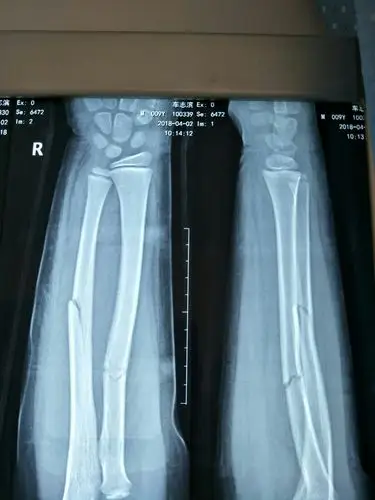

7岁孩子桡骨2根全部骨折了,正骨不理想,从x光片中明显看到错位,怎么办

下面是一些常见的前臂骨折x光片——对于年龄小的孩子,详细的临床查体

请大家看看张x光片,桡骨远端骨折复位前后